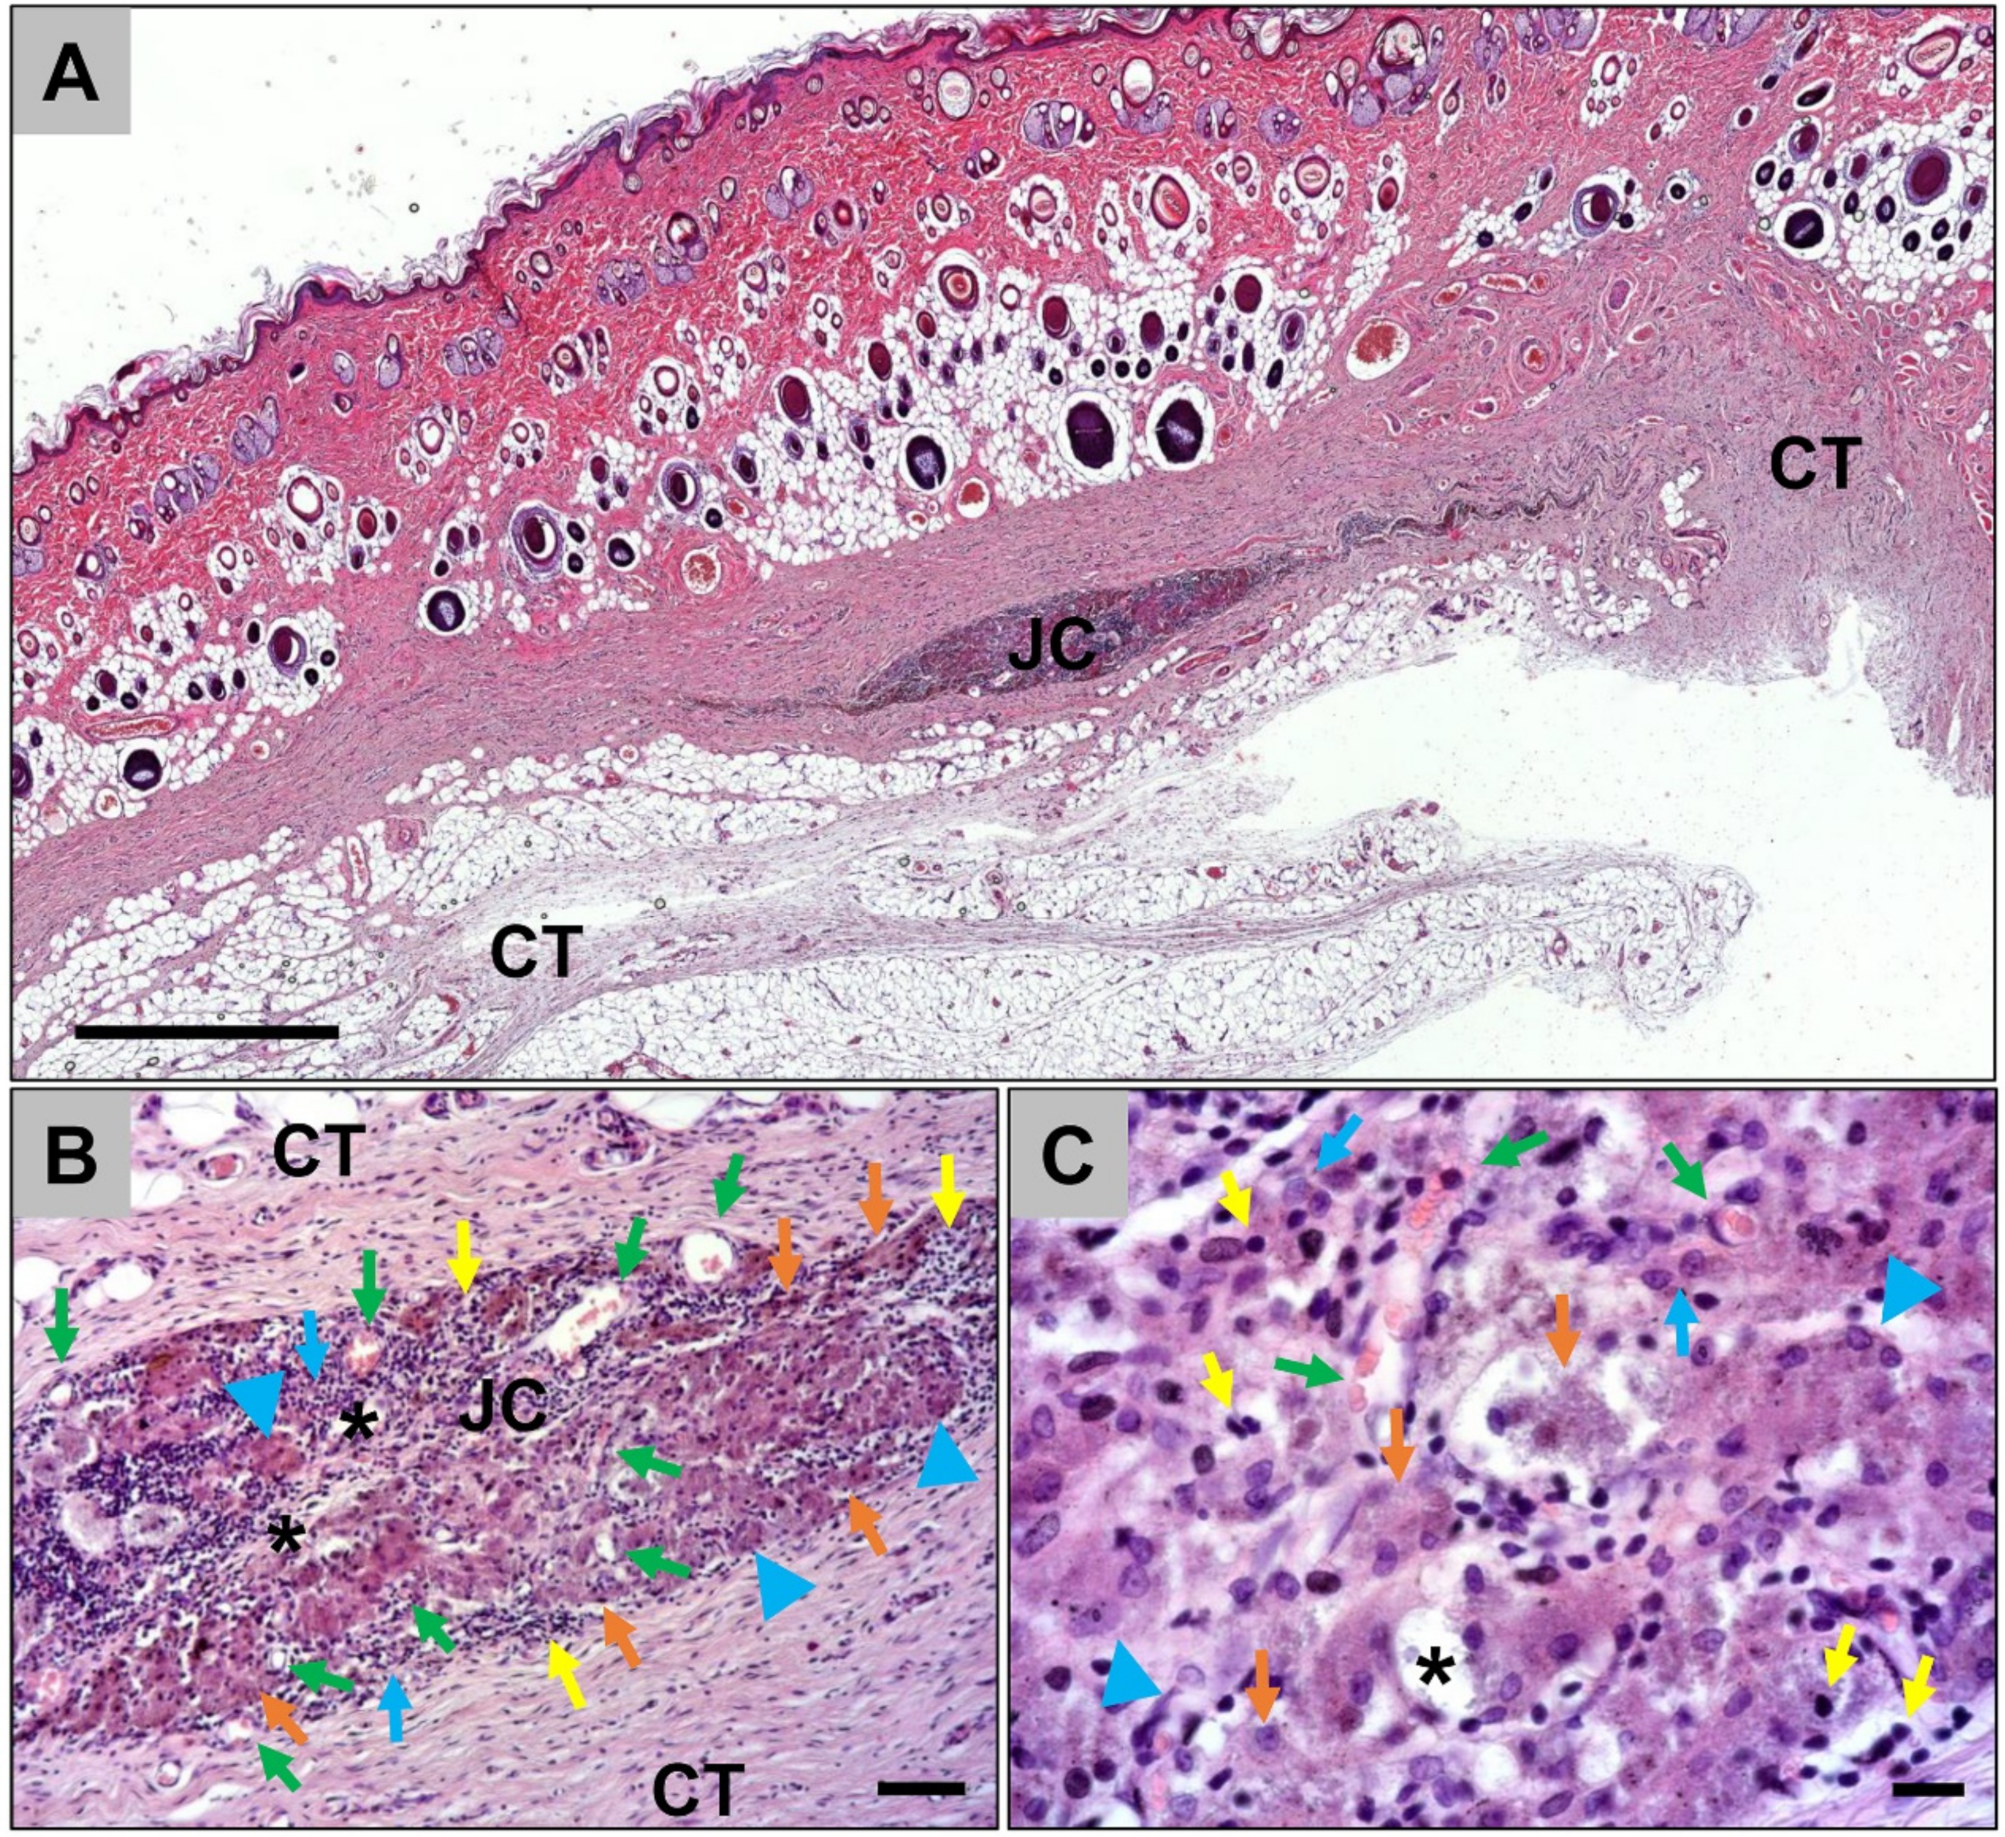

2.1.1. Histological Analysis of the Subcutaneous Implants

2.1.2. Histological Analysis of the Immune Response Within the Subcutaneous Tissue